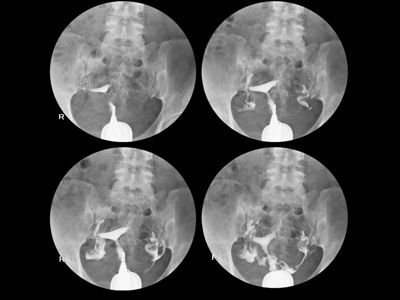

Hysterosalpingography (HSG): 5 Common Questions and Answers

Hysterosalpingography (HSG), also known as a “dye X-ray of the uterus,” is a special type of X-ray in which a...